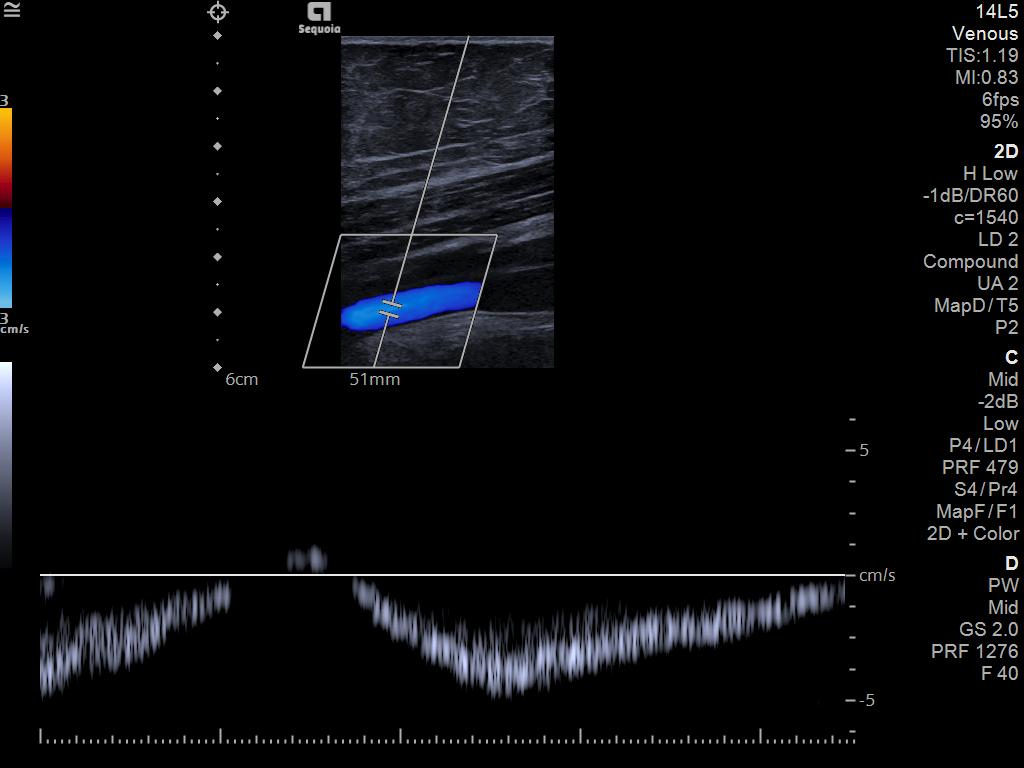

The ACUSON Sequoia is an advanced diagnostic tool that integrates cutting-edge technology and AI-powered applications to streamline diagnostic processes. This system is designed to cater to patient-specific needs, ensuring accuracy and efficiency in various clinical settings such as Radiology, OB/GYN, Shared Service and beyond.

The latest updates on ACUSON Sequoia use the power of groundbreaking AI for abdominal cases, includes advanced breast visualization to deliver new levels of image quality confidence, and tackles the toughest challenges in musculoskeletal imaging, all while saving your team from needless strain and pain.

Boost your clinical confidence with a system designed to enhance your expertise. The ACUSON Sequoia gives you the power to know more by maximizing the sensitivity and depth of your scans, while reducing variability across patients, systems and users.

ACUSON Sequoia’s InFocus imaging architecture eliminates the need for conventional focal zones to create a fully focused image faster than conventional systems. Our InFocus technology applies to all imaging transducers and exam types giving you consistent imaging across clinical segments. Some of the benefits are:

A clearer, deeper perspective with optimal acoustics for each clinical use case. Expand your assessment with advanced tools that take ultrasound beyond its traditional role.